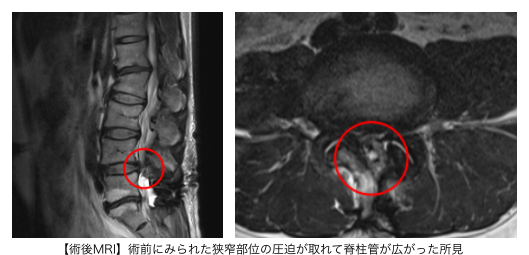

腰椎MRIからL4/5狭窄症が症状の原因と判断し、PEL(脊柱管狭窄症内視鏡下手術)を実施。神経修復効果を期待して、同時にPRP療法も行いました。

┃治療後の経過

術後1ヶ月、3ヶ月で、レントゲンを見ながらPRPを注射しました。手術後は徐々に痛みが緩和され、25日後には服薬せずに日常生活が送れるようになりました。

術前は15分程度歩いたら痺れが出ていましたが、症状緩和に伴い歩行距離が延伸。術前にはNRS10(強い痛み)と感じていたところ、手術から6ヶ月後には痛みも痺れもNRS0(痛みがない状態)となりました。